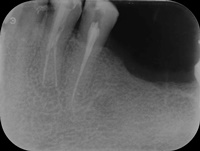

Reendo dolnej szóstki.

Wykonany zabieg resekcji wierzcchołka nie pomógł w ustąpieniu obajawów zapalnych. Skuteczne okazało sie dopiero reendo.